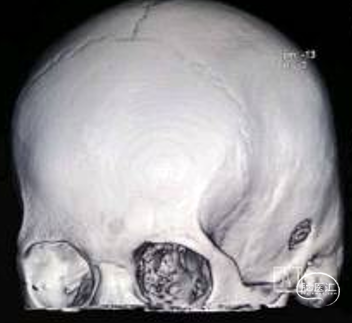

术中图片

颞骨钻孔,打磨内板使之成为“倒喇叭”状骨孔,Burr Hole外板内径11mm